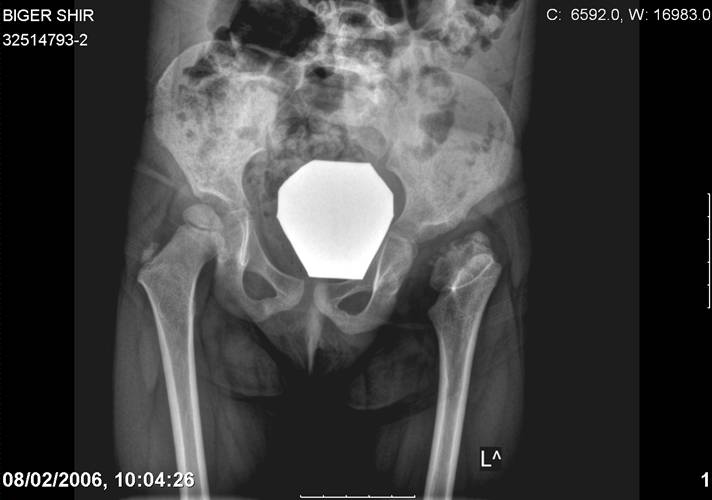

[Ortho] Врожденный вывих бедра

Navernoe Dega

Chto by ne byt goloslovnym posilau vam svoi sluchai gde sdelal vse chto napisal vyshe

Mark Eidelman